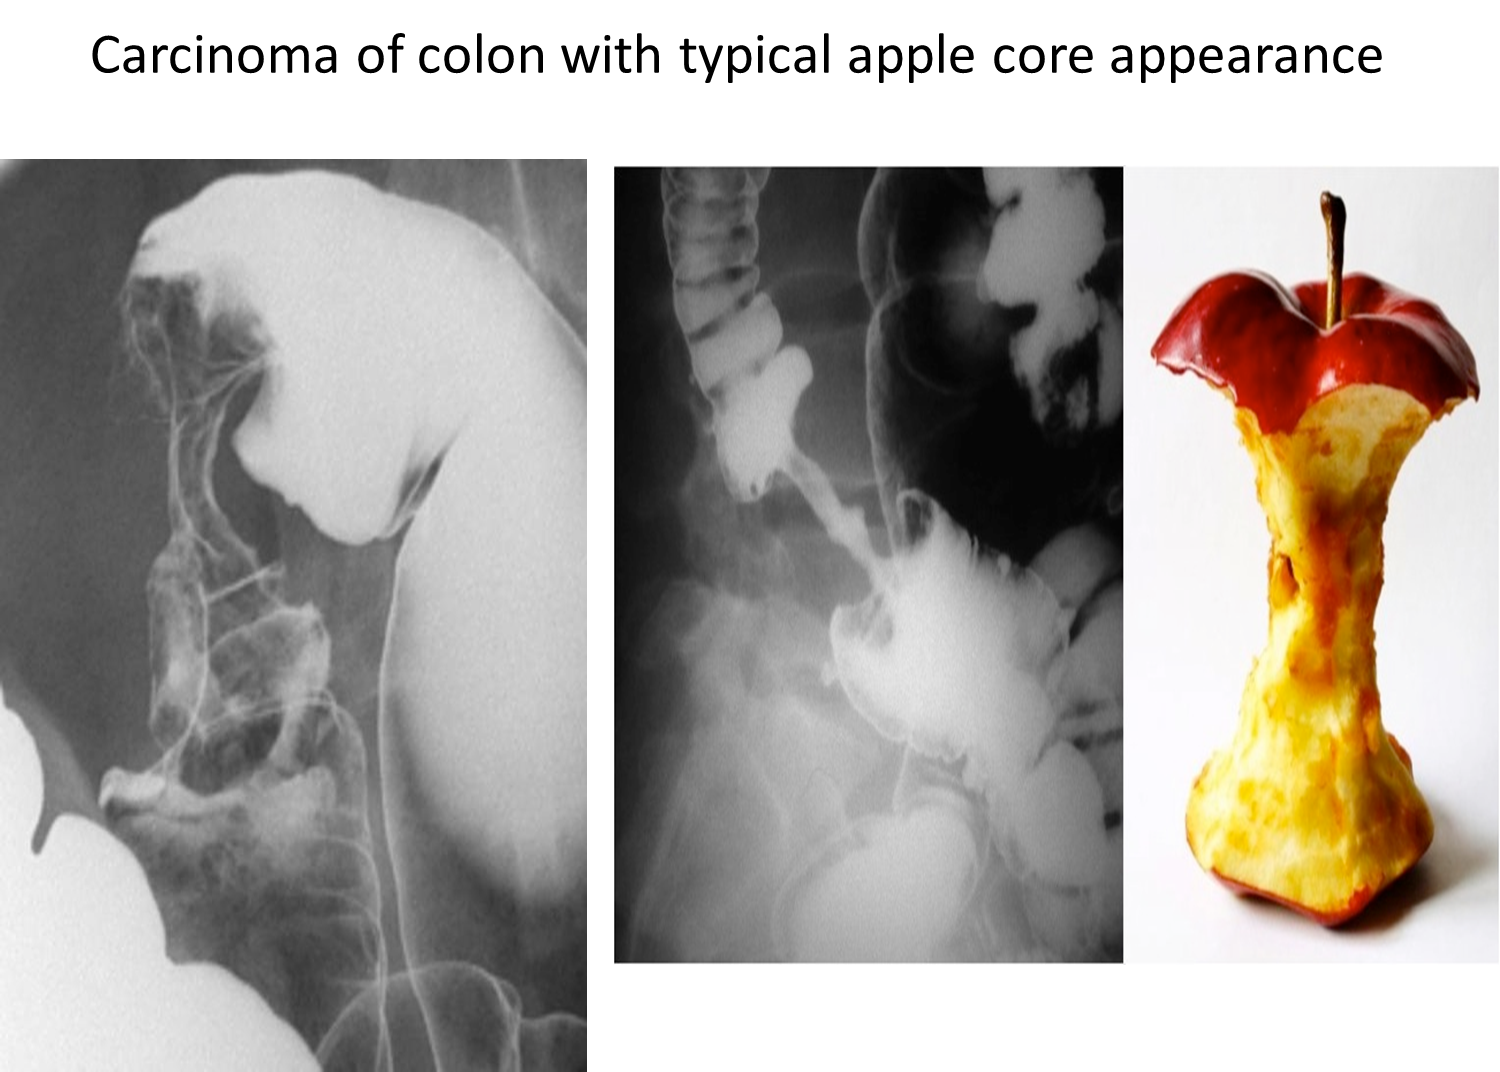

Colonic Carcinoma

apple core - bleeding per rectum - lose of weight - anaemia